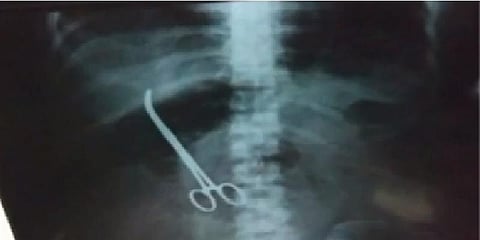

இதனால் அப்பெண் மறுபடியும் இதே மருத்துவமனையில் சிகிச்சை பெற வந்துள்ளார். அப்போது எக்ஸ்ரே எடுக்கும்படி மருத்துவர்கள் அந்தப் பெண்ணை அறிவுறுத்தியுள்ளனர். அந்தப் பெண் எடுத்த எக்ஸ்ரே மூலம் அதிர்ச்சியான தகவல் ஒன்று கிடைத்தது. அதாவது அவரது வயிற்றில் ஒரு கத்தரிகோல் இருப்பது தெரியவந்தது. இது அறுவைச் சிகிச்சை செய்த மருத்துவர்களின் கவனக்குறைவினால் நடந்ததாக தெரியவந்துள்ளது.

இதனையடுத்து அப்பெண் மருத்துவமனையில் உடனடியாக அனுமதிக்கப்பட்டார். மருத்துவமனை நிர்வாகம் அந்தப் பெண்ணின் வயிற்றிலுள்ள கத்தரிகோலை அகற்றும் பணியை மேற்கொண்டுள்ளனர்.